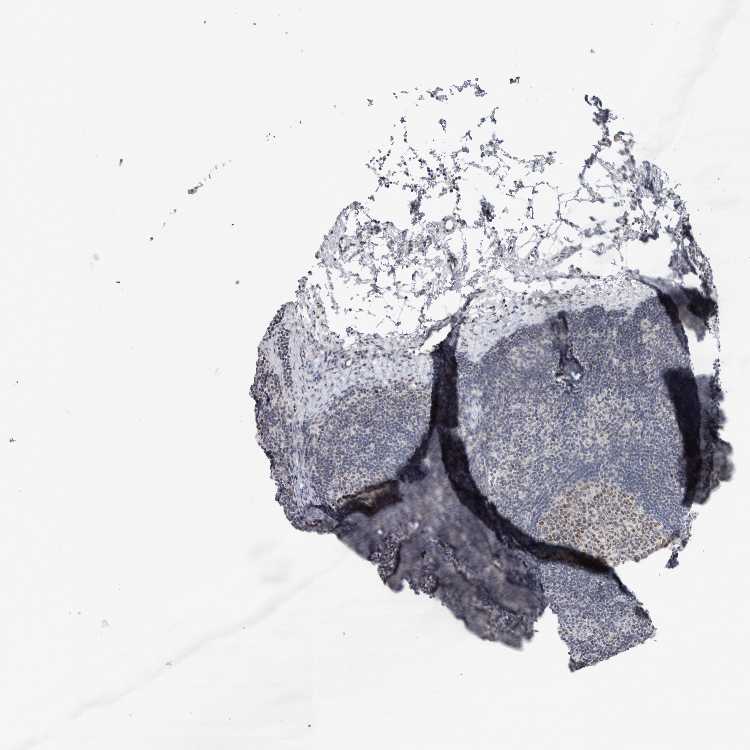

TISSUE PRIMARY DATA LYMPH NODE Show tissue menu

Lymph node

LYMPH NODE - Antibody stainingi

Antibody staining in the annotated cell types in the current human tissue is reported as not detected, low, medium, or high, based on conventional immunohistochemistry profiling in selected tissues. This score is based on the combination of the staining intensity and fraction of stained cells.

Each image is clickable and will lead to virtual microscopy that enables deeper exploration of all samples and also displays staining intensity scores, fraction scores and subcellular localization as well as patient and tissue information for each sample.

Antibody HPA023323Antibody HPA028455

Germinal center cells MediumMedium

Non-germinal center cells Not detectedMedium